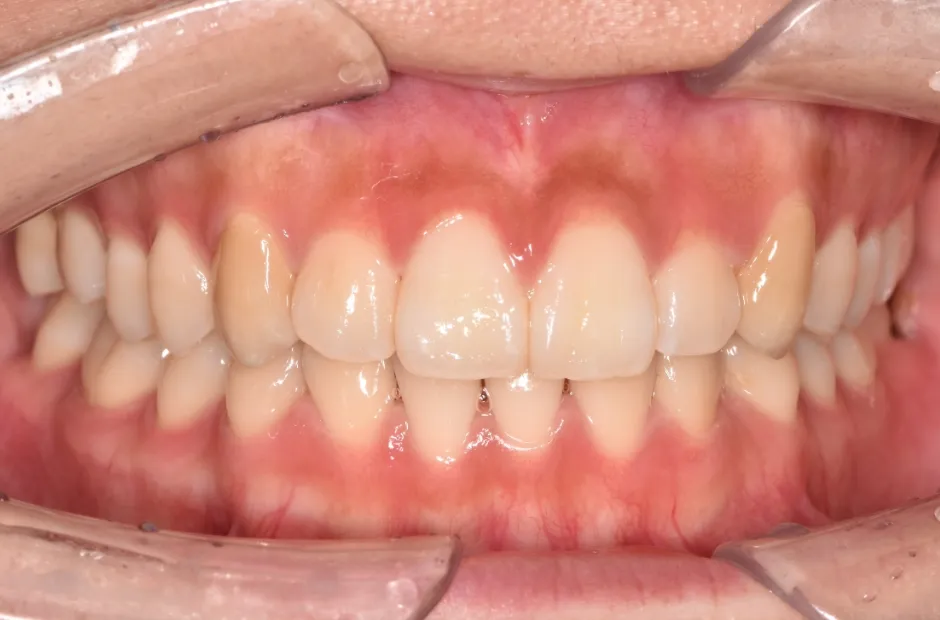

叢生

| 診断名・主訴 | 叢生 |

|---|---|

| 年齢・性別 | 43歳・女性 |

| 治療期間・回数 | 2年7か月 27回 |

| 治療に用いた主な装置 | 舌側矯正 |

| 抜歯部位 | 両顎4,4 |

| 治療費 | 100万円(税抜) |

| リスク・副作用 | 装置による違和感・疼痛・歯肉退縮・歯根吸収・虫歯のリスクなど |